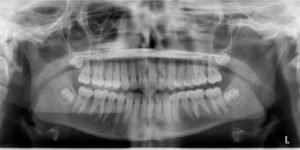

A 13-year-old female presents with a chief complaint that “My teeth aren’t in.”